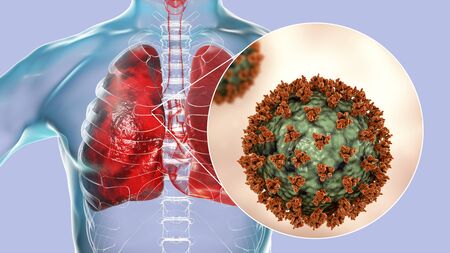

Coronavirus disease COVID-19 virus infection in human lungs, new corona virus infection or COVID ( novel Coronavirus 2019 disease, COVID-19, nCoV, SARS-Cov-2 ) pandemic outbreak as respiratory syndrome

Coronavirus disease COVID-19 virus infection in human lungs, new corona virus infection or COVID ( novel Coronavirus 2019 disease, COVID-19, nCoV, SARS-Cov-2 ) pandemic outbreak as respiratory syndrome